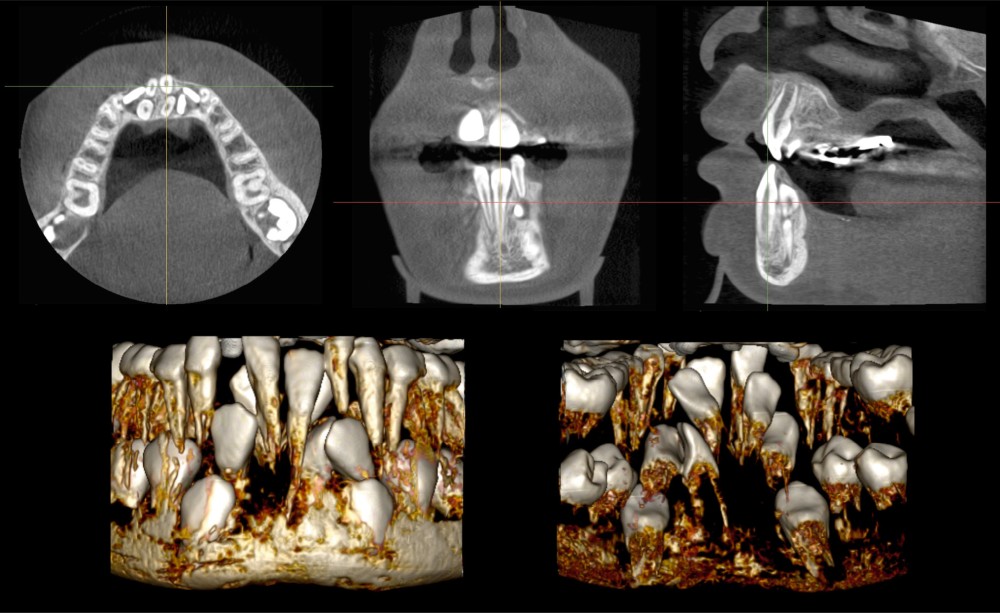

Nous suivons en orthodontie à l’hôpital de la Pitié-Salpêtrière une patiente de 9 ans qui présente un retard d’éruption dentaire inexpliqué à la mandibule : en bouche, la seule dent permanente du secteur incisivo-canin est la 41. La radiographie panoramique laisse suspecter la présence de germes surnuméraires. Une imagerie CBCT est prescrite et analysée classiquement via les vues multiplanaires (MPR) et les reconstructions volumiques basées sur des seuillages de niveau de gris (fig. 1).

L’analyse de l’imagerie CBCT est rendue difficile par le nombre important de dents surnuméraires présentes dans le secteur incisivo-canin mandibulaire. En particulier, la reconstruction volumique ne permet pas d’appréhender finement la position des différentes dents et de leurs racines. Cela complique l’établissement du plan de traitement, devant établir quelles sont les dents à avulser et celles à tracter avec un appareillage orthodontique. Cette décision de traitement serait grandement facilitée par des informations tridimensionnelles supplémentaires sur la forme des différentes dents, leur position tridimensionnelle ou encore leur édification radiculaire.